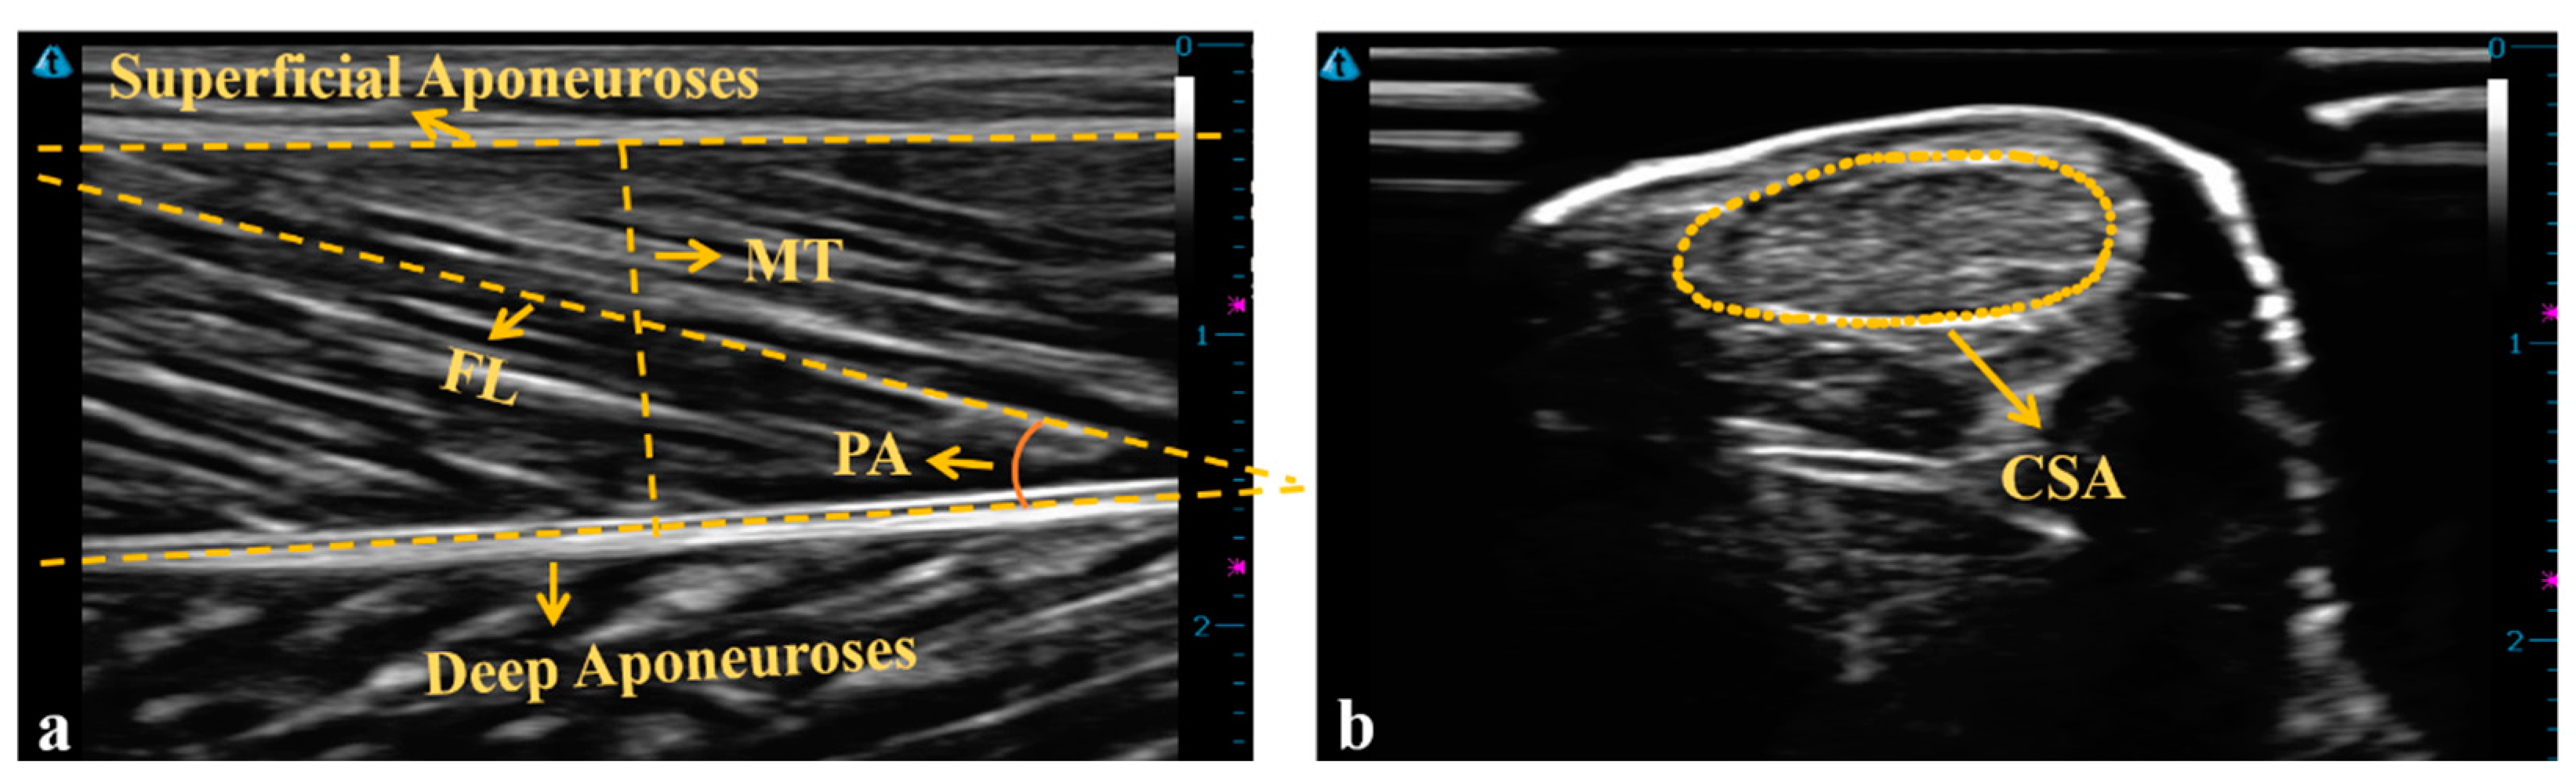

2.2. Instrumentations

2.4. Data Analysis

| FL (mm) | 67.3 ± 12.7 | 62.5 ± 7.6 | 55.9 ± 2.0 * | 0.029 | 0.187 |

| normalized FL | 0.36 ± 0.48 | 0.18 ± 0.03 | 0.16 ± 0.01 * | 0.015 | 0.237 |

| muscle thickness (mm) | 16.8 ± 1.5 | 17.3 ± 2.4 | 18.9 ± 1.9 | 0.065 | 0.183 |

| pennation angle (°) | 16.2 ± 1.9 | 18.9 ± 2.8 | 19.3 ± 2.4 * | 0.008 | 0.280 |